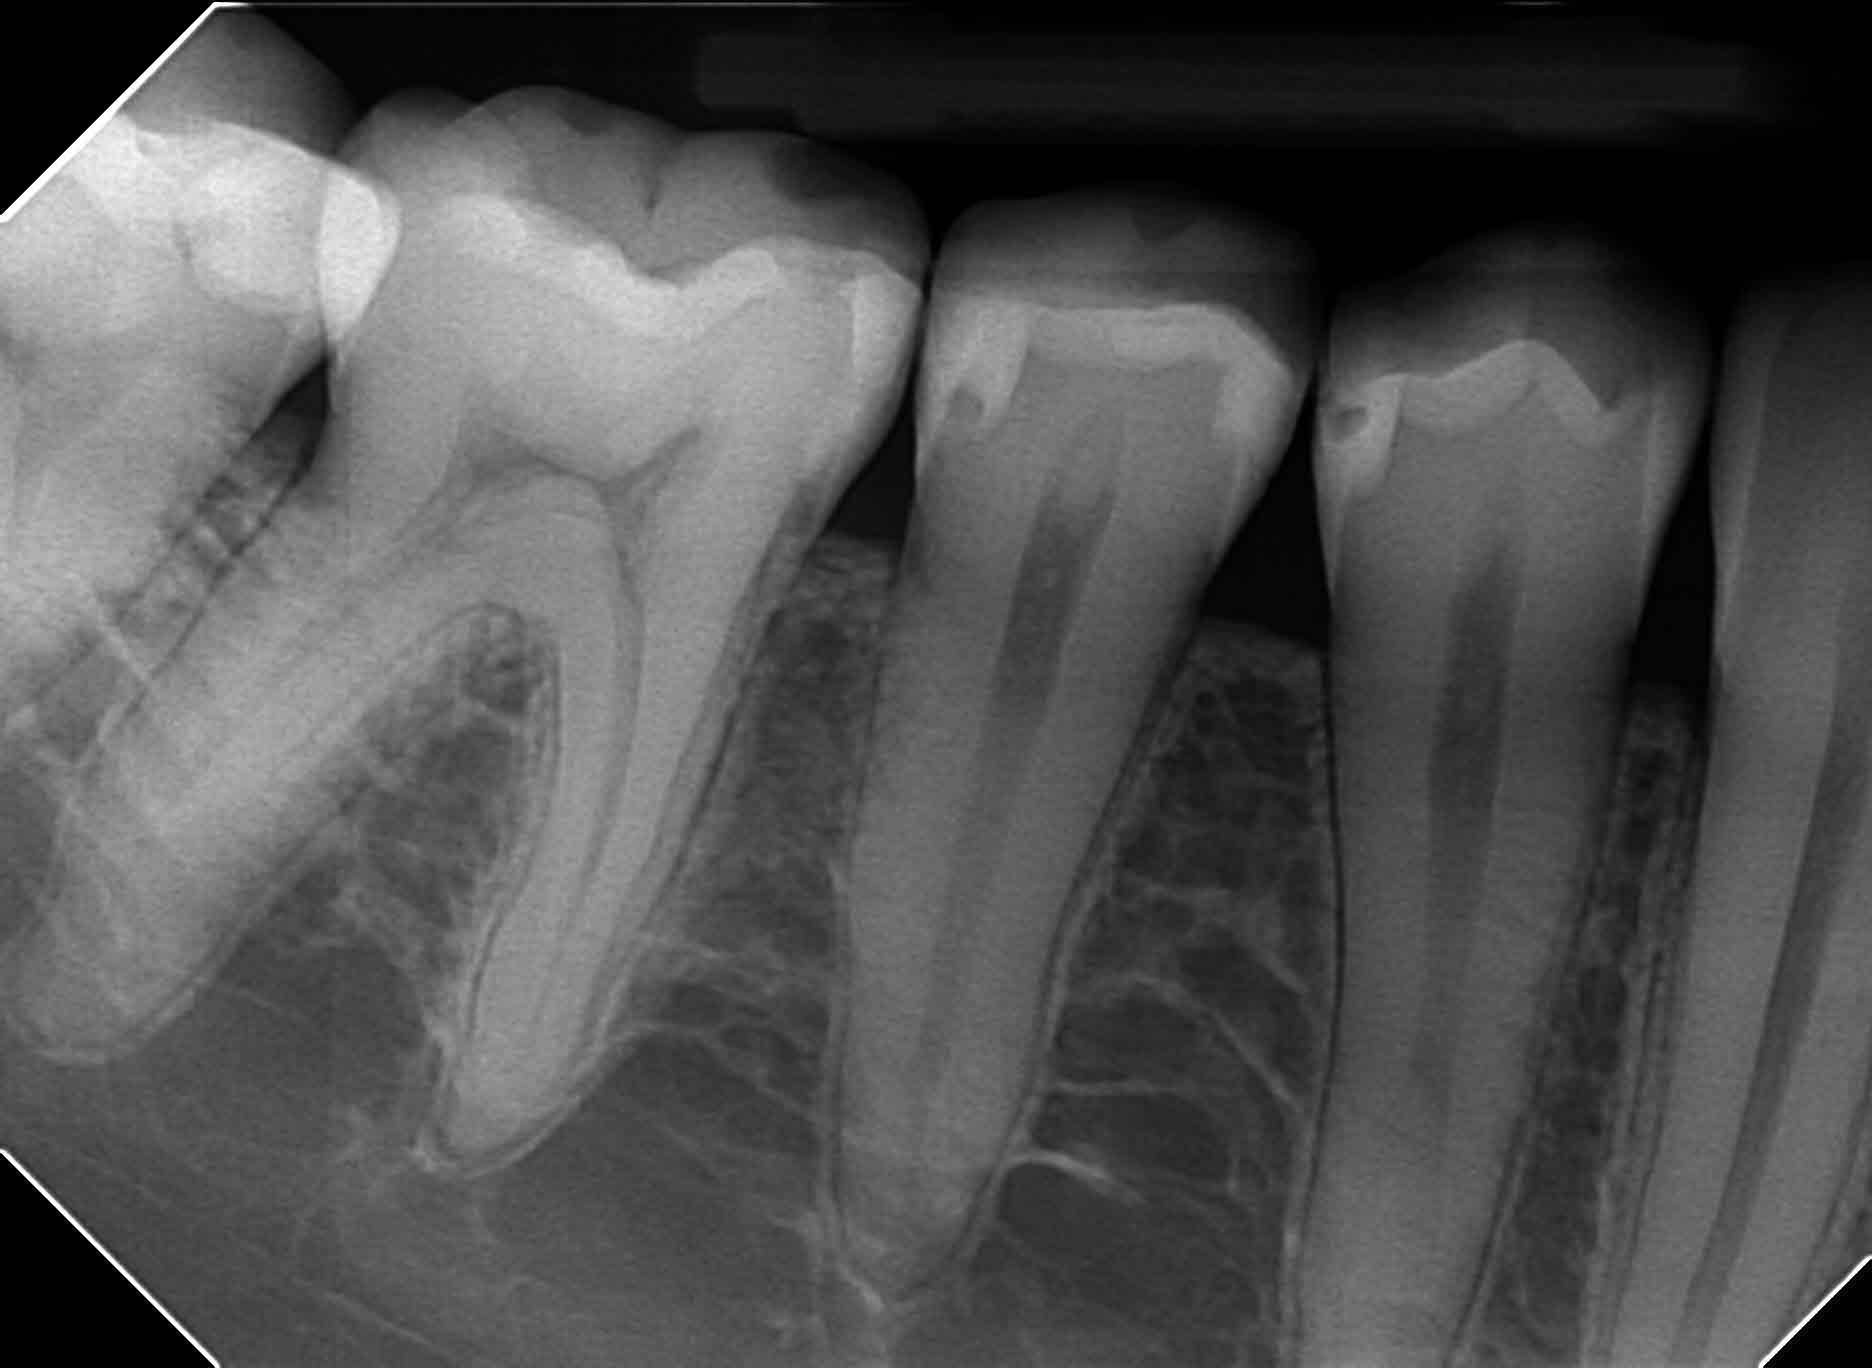

Fogászati intraorális röntgen

Abban az esetben, mikor csak egy vagy két fogat szükséges vizsgálni, akkor úgynevezett szájüregi felvétel, kisfelvétel készül. Ezek a felvételek digitális módon készülnek, ennek következtében a pácienst nagyon minimális sugárterhelés éri.

Az intraorális felvétel jóval részletgazdagabb, mint a panoráma felvétel. Ilyen röntgen kép készül a gyökérkezelések előtt, közben és a gyökértömés ellenőrzésekor. Tömések széli záródását, és az apró a fog oldalsó részén elhelyezkedő szuvasodást is ki tudja mutatni.